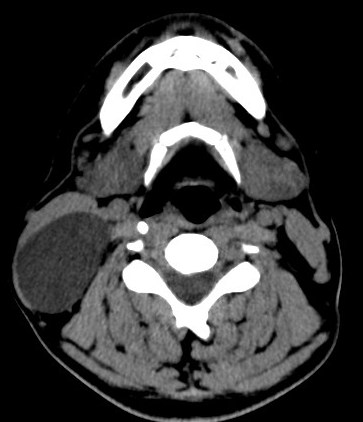

BRANCHIAL CLEFT CYST